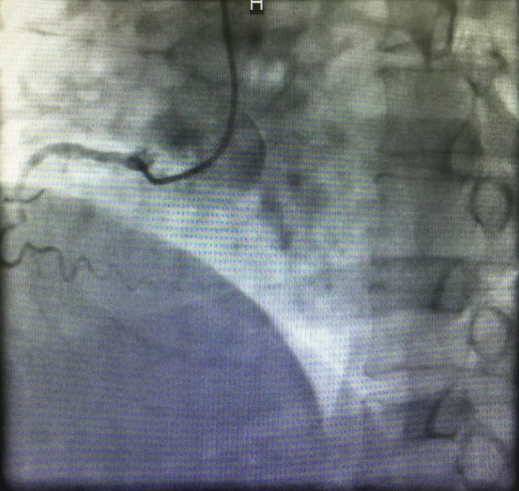

心内三完成21点游戏攻略站 首例逆向开通冠脉CTO病变